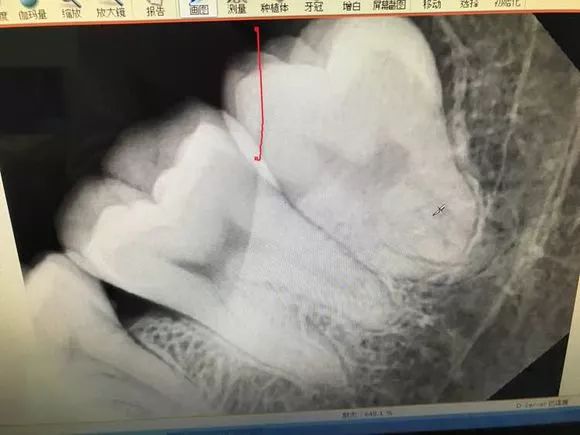

传说中收费14000的牙长这样子——

最后介绍一下,牙根弯曲,骑在下颌管上的智齿...由于下颌管内神经丰富,拔除的时候需要极度小心,而且看长相也知道这种模式的拔牙,非常难也非常贵!

1.2 恰当检查 包括高质量的X线片,它不仅能提供牙齿的清晰图像,牙根的轮廓和解剖以及牙周骨质情况,还能提供牙齿与邻牙和其他结构之间的关系,其中尤其是下颌骨下缘、下颌骨升支以及下牙槽神经束之间的关系。

2.2 术前评价 在有下牙槽神经损伤可能性时,应该通过术前的放射片来评价下牙槽神经损伤的风险是低、中、高或非常高,给患者的警告应能体现这种评价结果。